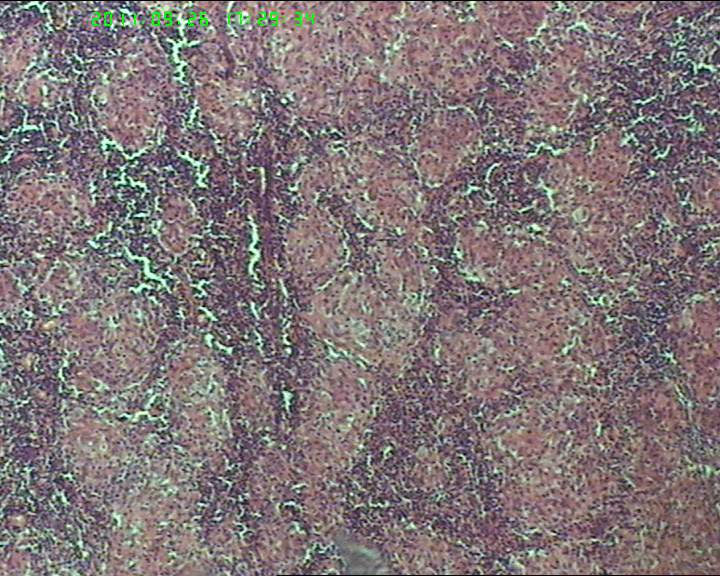

21岁女性左侧颌下淋巴结,该诊断什么?

灰白不整形肿物一个,大小3.5*2.5*2cm,包膜完整。

21岁女性左侧颌下淋巴结,该诊断什么?图4

慢性肉芽肿性炎症,形态学倾向结节病,但是作为病理工作者对于这样的病例,再结合咋们国情,还是建议临床除外增殖性结核后再考虑结节病。

肉芽肿性炎症,倾向结节病。

首选结节病

从病原学找根据,找不到根据就要考虑结节病了。